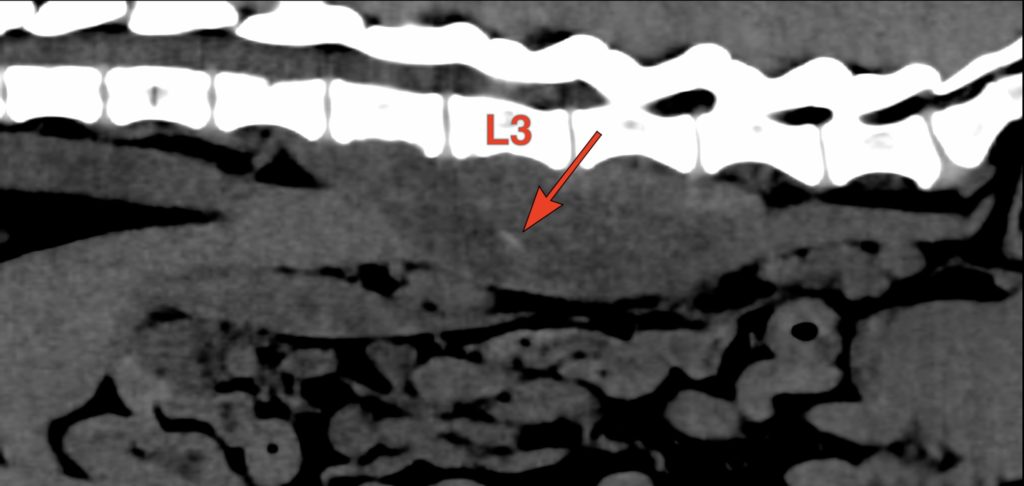

Affection touchant quasi exclusivement le chien, la migration de corps étrangers de type épillets peut provoquer des abcès profonds, dont la localisation peut être problématique. Fréquemment ces corps étrangers peuvent provoquer des abcès pulmonaires, des pyothorax (infection thoracique), des abcès sous-lombaires (avec infection vertébrale), etc…

Grâce au scanner qui améliore beaucoup la précision de la recherche du corps étranger, nous pratiquons de nombreuses interventions sur ces abcès profonds. Les corps étrangers sont localisés en cours de chirurgie grâce à de l’échographie per-opératoire, permettant de réduire les risques et le délabrement musculaire.